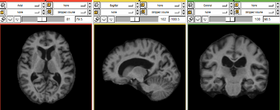

Output - Brain mask split at midsagittal plane overlaid on original image.

Output - Skullstripped results.